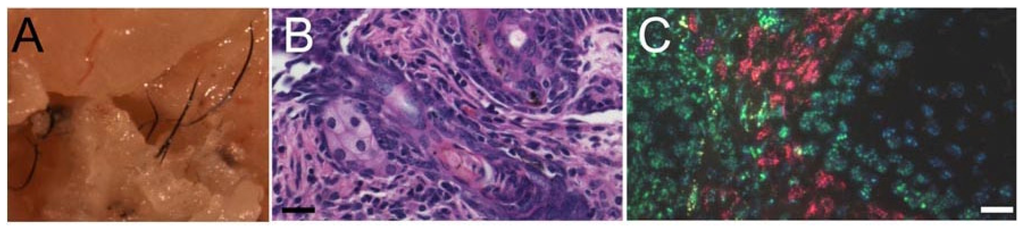

- Thangapazham, R.L.; Klover, P.; Wang, J.A.; Zheng, Y.; Devine, A.; Li, S.; Sperling, L.; Cotsarelis, G.; Darling, T.N. Dissociated human dermal papilla cells induce hair follicle neogenesis in grafted dermal-epidermal composites. J. Investig. Dermatol 2014, 134, 538–540. [Google Scholar]